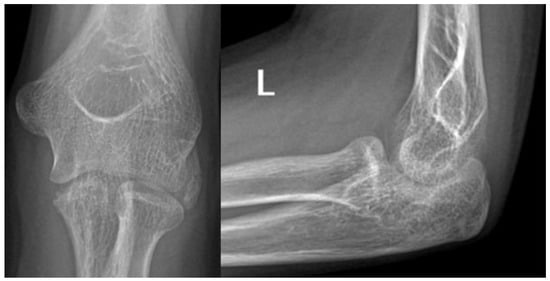

At the age of 13, another injury occurred, and the child complained of a sprain prior to the injury. X-ray imaging showed a posterior elbow dislocation without signs of a fracture (Figure 5). Under anesthesia, the luxation was repositioned. Following repositioning, an image review was performed, and no suspected fracture area was identified. A long upper limb cast was placed for two weeks.

Figure 5.

Imaging of the posterior dislocation at age 13, image (A) showing the luxation upon ebow extension and (B) from a lateral view in flexed position.

He suffered another elbow trauma due to a fall at the age of 14, resulting in pain and dislocation. X-rays showed no recent fracture, but a 5 mm rounded bone fragment was visible. MRI was requested for diagnostic purposes and further exploration (Figure 6). The results indicated that the fragment originated from the coronoid process and that the elbow was in a dorsally subluxated position. With regard to the instability, the exploration of the joint with debridement and reconstruction was proposed. A CT scan was performed for surgical planning, which yielded equivalent results to the MRI. A summary of events can be seen in Table 2.

Figure 6.

X-rays showing fragmentation, highlighted by the pink circle (A,B). Subluxation is visible on the MRI pointed at with pink arrows (C).